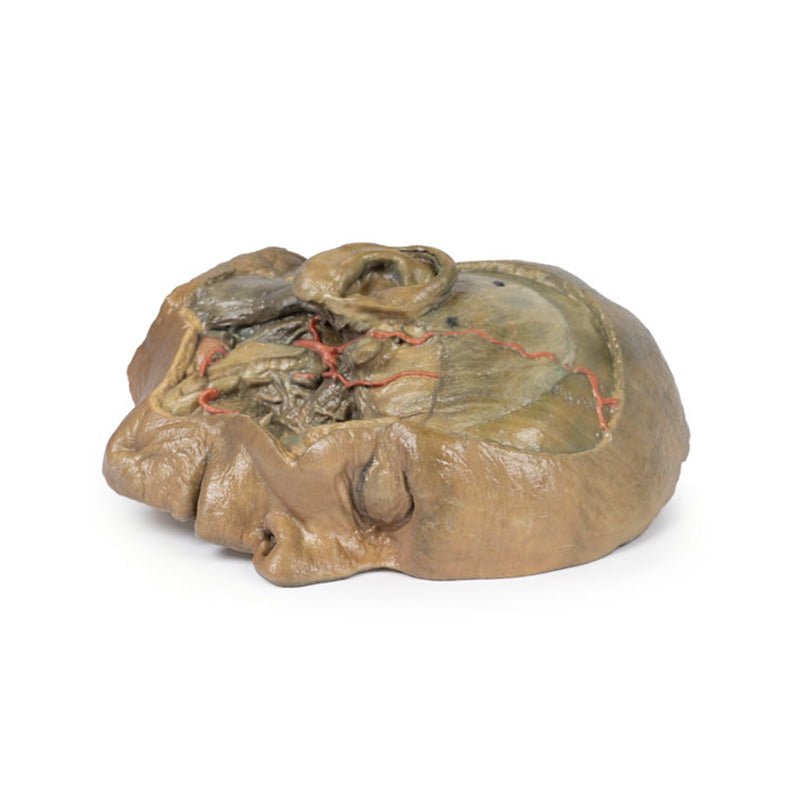

3D Printed Sagittal Section of Head with Infratemporal Fossa Dissection

This 3D model provides a combined midsagittal section through the head and

superior neck coupled with a deep dissection into the infratemporal fossa

region and superficial dissection of the scalp.

On the opposing side of the model, a superficial and deep dissection has

opened a large window into the anatomy of the lateral scalp and infratemporal

fossa. Across the scalp there is a well preserved posterior auricular nerve

and superficial temporal artery highlighted on the superficial surface of the

temporalis muscle. Anteriorly, the temporalis has been dissected to expose

the deep temporal arteries arising from across the maxillary artery.